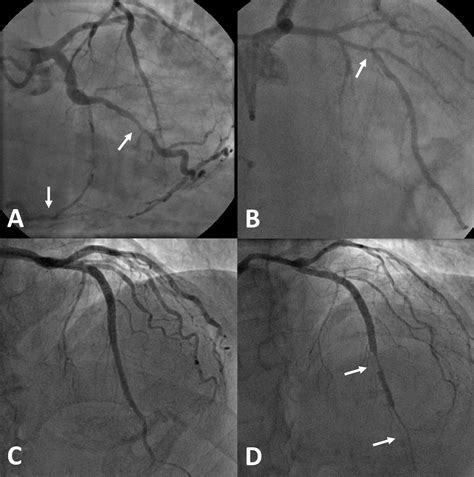

The FFR test in cardiology plays a pivotal role in the diagnosis and management of coronary artery disease. Traditional diagnostic methods, such as angiography, provide a visual representation of the arteries but do not always accurately reflect the functional significance of a stenosis. FFR, on the other hand, offers a functional assessment of blood flow, helping cardiologists make more informed decisions.

• Assessing the functional significance of intermediate coronary stenoses identified during angiography.

• Assessing the hemodynamic significance of coronary lesions in patients with complex coronary anatomy.